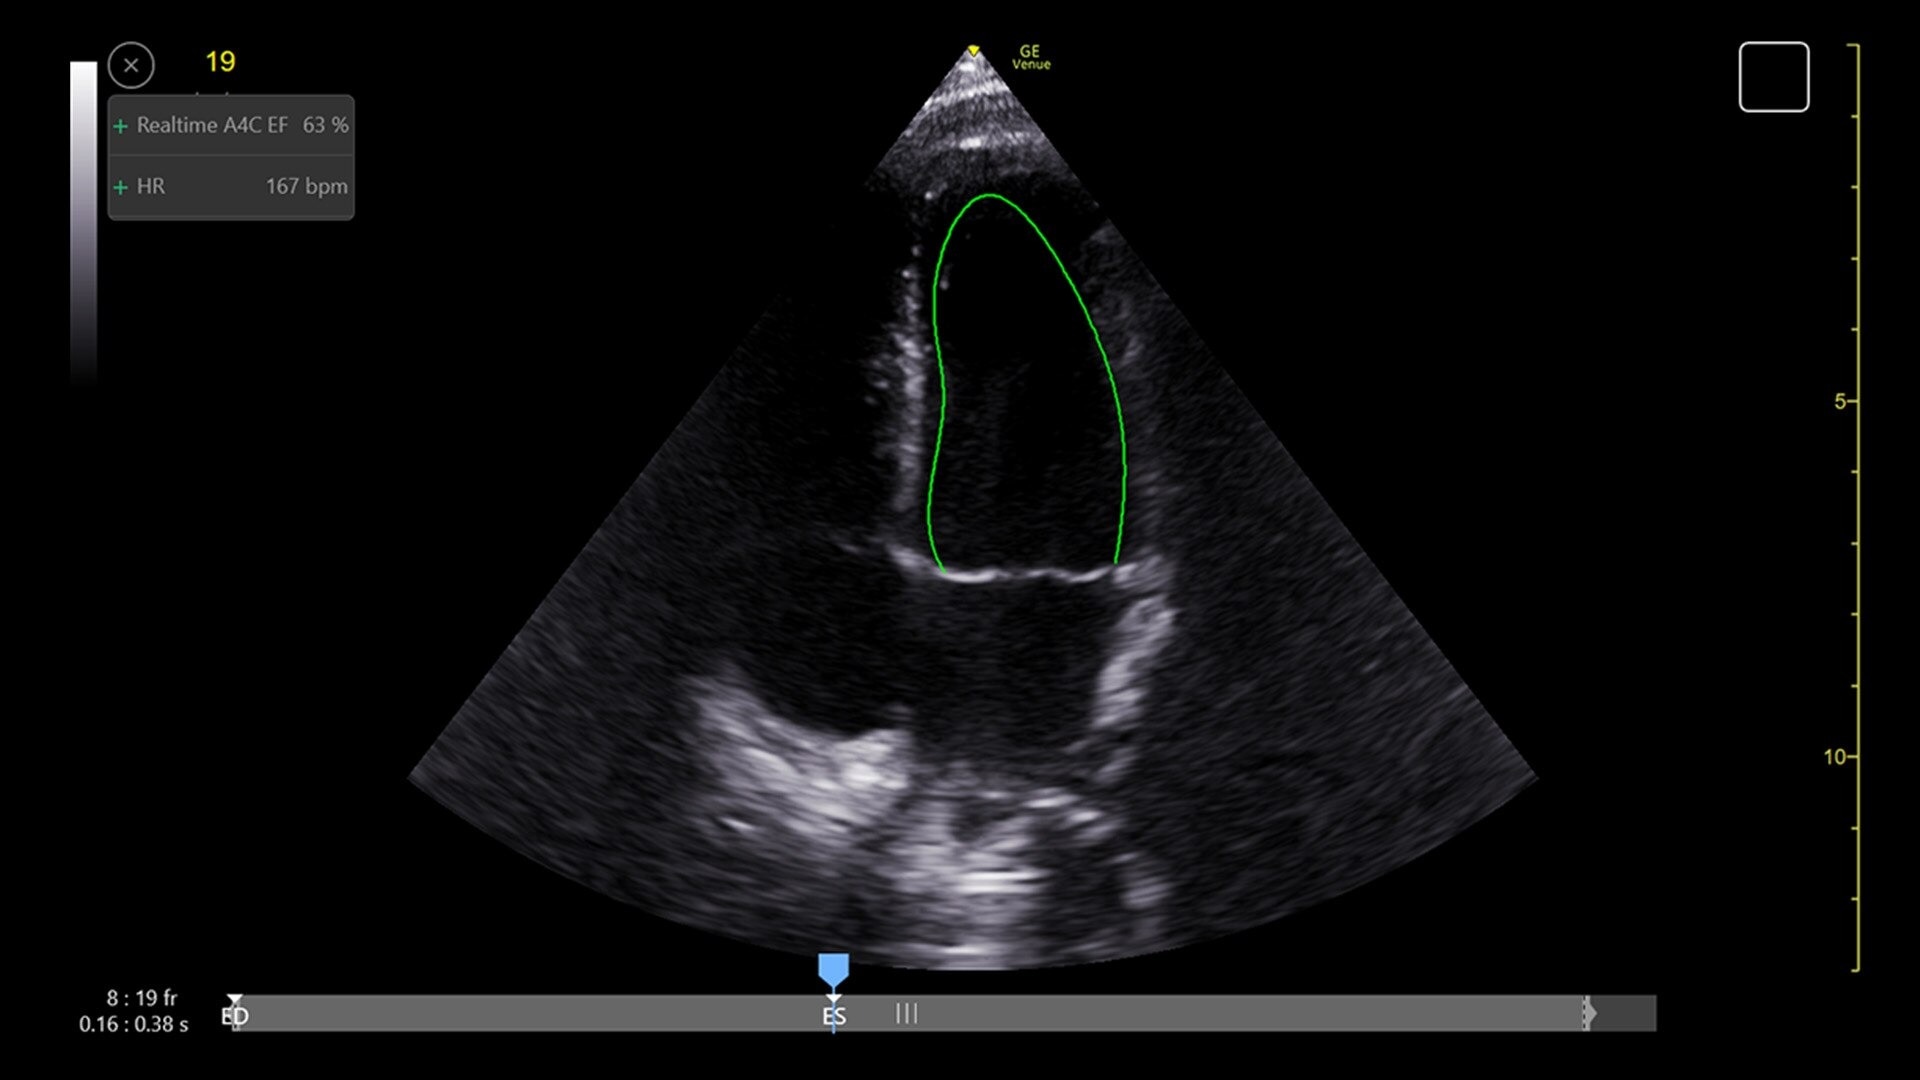

Automated tools

Simplify your workflow with AI-enabled clinical tools.

Helping drive consistency from user to user (whether one is an ultrasound novice or expert), Venue Fit features AI-enabled resources that help clinicians work smarter and more efficiently. Utilizing proprietary algorithms, we synthesize data from numerous patients to ensure accurate calculations for clinical confidence.